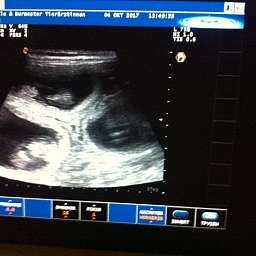

4.10.2017, 35.Tag: Der Ultraschall brachte 5 kleine Wunder zutage. Gesund und munter mit Herzschlag und Bewegung. Elise meisterte alles mit Bravour. Mit Ruhe, Vertrauen und Engelsgeduld ließ sie alles über sich ergehen. Ich bin sehr stolz auf unsere Kleine. Es sind also mindestens 5 Welpen unterwegs. Schaut doch mal: